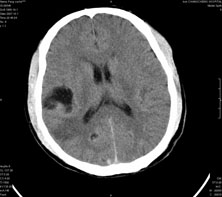

男,41岁,间断抽搐1小时,失神5分钟,bp130/90mmhg。低密度区ct值约16hu。

脑实质见多发散在的钙化点,左顶叶见一囊变灶,多考虑脑囊虫。

脑囊虫,部分囊内见头节。

脑实质见多发散在的钙化点,右颞、顶叶见囊性灶,考虑脑囊虫。

多发的囊泡(多发囊型)+多发的钙化(慢性钙化型)=混合型

顶叶最大的囊直径2.2cm,如果考虑囊虫的话,囊是不是有点儿太大了?